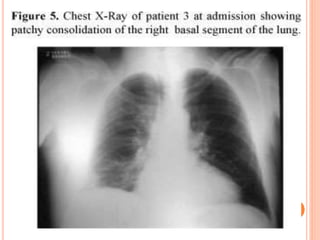

DIAGNOSIS IMAGING

 unilateral pattern of alveolar infiltrates or

bronchopneumonia predominates then progress bilateral

 Findings are usually confined to a single lobe with lower

lobe involvement more frequent than middle or upper

lobe involvement Up to a quarter of patients may

demonstrate a

 small to moderate-size pleural effusion.

 Hilar or mediastinal lymphadenopathy is an uncommon.